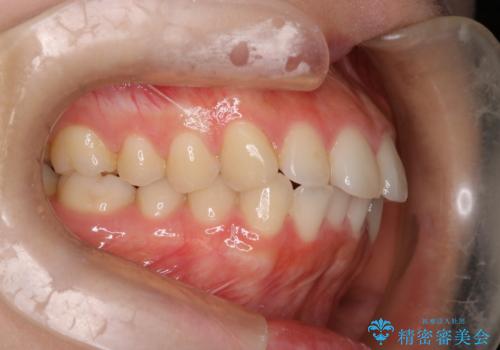

【インビザライン】前歯を下げたい

- 前歯が出ていることを主訴に来院されました。

奥歯を後ろに動かしながらスペースを作ることで、前歯を下げることができ患者さんにも満足していただきました。

治療中に顎間ゴムを使用していただいたおかげで、スムーズに治療を行うことができました。